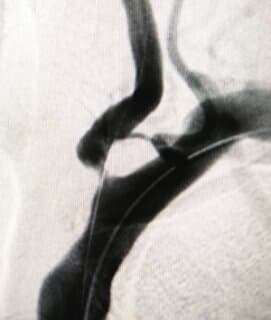

经过韩献军团队的积极治疗,孙先生言语不清症状得到明显改善。但患者的颈椎和颅脑CTA+CT血管成像显示:右侧颈内动脉起始处局部管腔重度狭窄,两侧椎动脉V4段局部中-重度狭窄;颅脑及颈部动脉多发血管斑块形成伴管腔不同程度狭窄。

显微镜荧光造影下见颈总动脉、颈内动脉、颈外动脉、甲状腺上动脉通畅,充盈良好,动脉壁吻合口无明显渗血。手术成功!